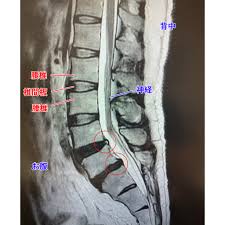

骨盤は、横から見た時におおよそ35度前傾しているのが良い姿勢と言われています。

この角度がきつくなっている方、いわゆる反り腰や出尻のようになっている状態で腰痛に悩まれている方は非常に多いです。

また、後ろから見たときには、肩の高さや肩甲骨の高さ、腰骨の高さや背骨の曲がり方などを診て背骨の歪みや骨盤の歪みを診ます。